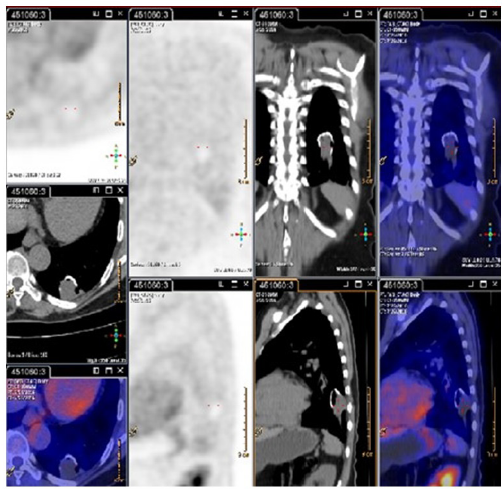

Ante estos hallazgos se completan estudios para descartar malignidad. La fibrobroncoscopia con lavado bronco-alveolar fue negativa para malignidad o infecciones. El PET CT evidenció una lesión cavitada en lóbulo inferior izquierdo sin aumento anormal del metabolismo (figura 2).

Se completaron los estudios para descartar neoplasia pulmonar y lesión esofágica. El PET CT mostraba una lesión sin aumento anormal del metabolismo, localizada en lóbulo inferior derecho, que medía 28 x 18 x 18 mm, sin otros hallazgos anormales.